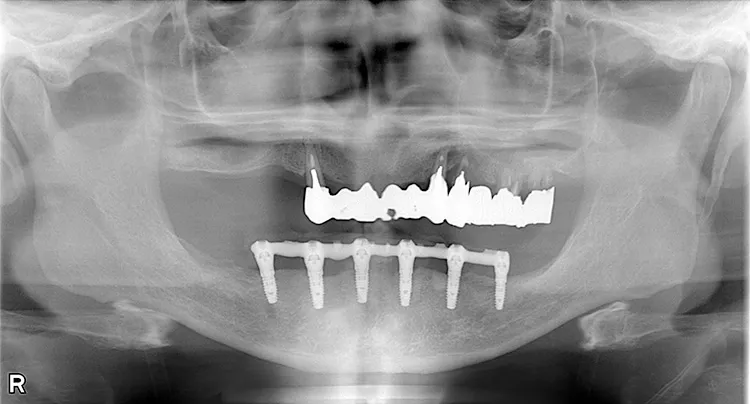

ボーンアンカードブリッジの下顎症例です。同じようにインプラント6本で上部構造を支えることができます。